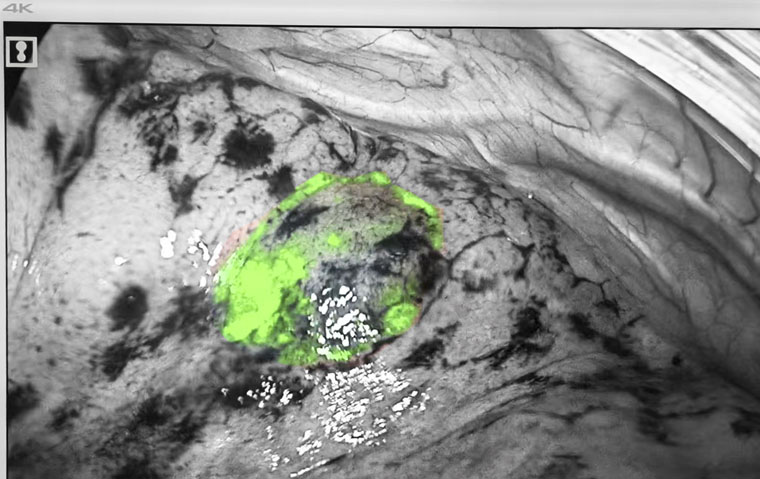

荧光显影标记

手术在麻醉三科贾丽主任团队全程保障及东院手术室护理团队的协助下进行。黄超主治医师操作电磁导航支气管镜,胸科内镜室张金泽技师长、边媛媛主管护师全力配合。患者全麻后,医疗团队经气管插管进镜,在电磁导航的实时指引下分别到达两处病灶位置,并将荧光显影剂通过内镜鞘管分别滴注至两处病灶定位标记,整体操作时间仅10余分钟。定位后,胸腔镜手术随即进行。荧光模式下,在肺表面即可看到定位的荧光显影标记,术者对病灶进行精准切除。术中快速冰冻病理显示,右肺上叶前段楔形考虑微浸润性腺癌,肺上叶后段楔形肺组织内可见纤维化结节,周边局灶肺泡上皮非典型增生,最终石蜡病理回报吻合口切缘阴性,表示边缘未发现肿瘤细胞,手术已完整切除病变。